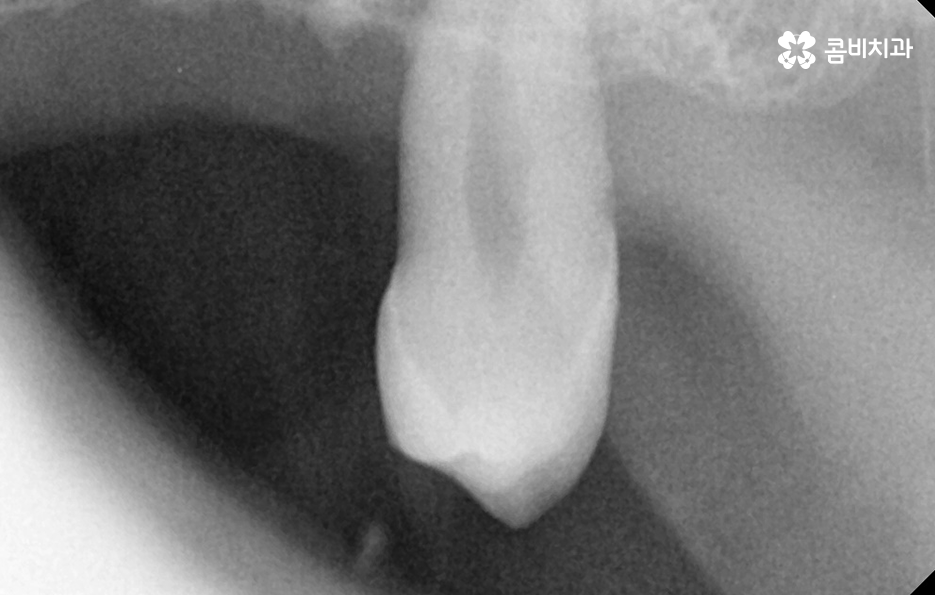

노년기에 치아 상실이 증가하는 큰 원인은 치주염의 장기적 누적 효과로서 치주염은 잇몸 염증이 잇몸뼈까지 파고들어 뼈를 녹여 치아를 지탱하지 못하게 만드는 병으로 젊을 때는 잇몸이 어느 정도 회복되기 때문에 크게 느껴지지 않지만, 나이가 들수록 회복 속도는 느려지고 염증은 더 빨리 확산되며 잇몸뼈가 한 번 녹기 시작하면 다시 원래 그대로 회복되는 것은 사실상 어렵기 때문에 치아는 점점 흔들리고, 결국 발치까지 이어질 수 있어요

그리고 충치 재발 또는 오래된 보철물의 노후화 문제도 큰데 젊은 시절 충치 치료나 크라운, 브릿지 등을 했더라도 노년이 되면 재 치료가 필요한 경우가 많으며 보철물은 영구적이지 않기 때문에 접착력이 약해지거나 잇몸이 내려가면서 보철물 경계부위에 충치가 다시 생길 수 있고 특히 치아 뿌리 부분에 생기는 충치는 진행 속도가 빨라 치료가 어려운 경우도 많아서 보철물 아래 치아가 불안정해지면 결국 발치해야 하는 상황이 생기는 거예요.